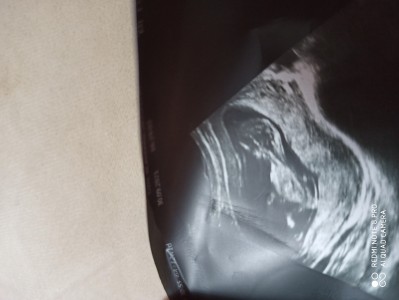

kizlar 12 haftalık gebeyim cinsiyetten anlayan var mi

12 haftalik gebelik cinsiyet yorumu

Erkek bence kafa yapisi o sekilde duruyir

bana Erkek gibi geldi